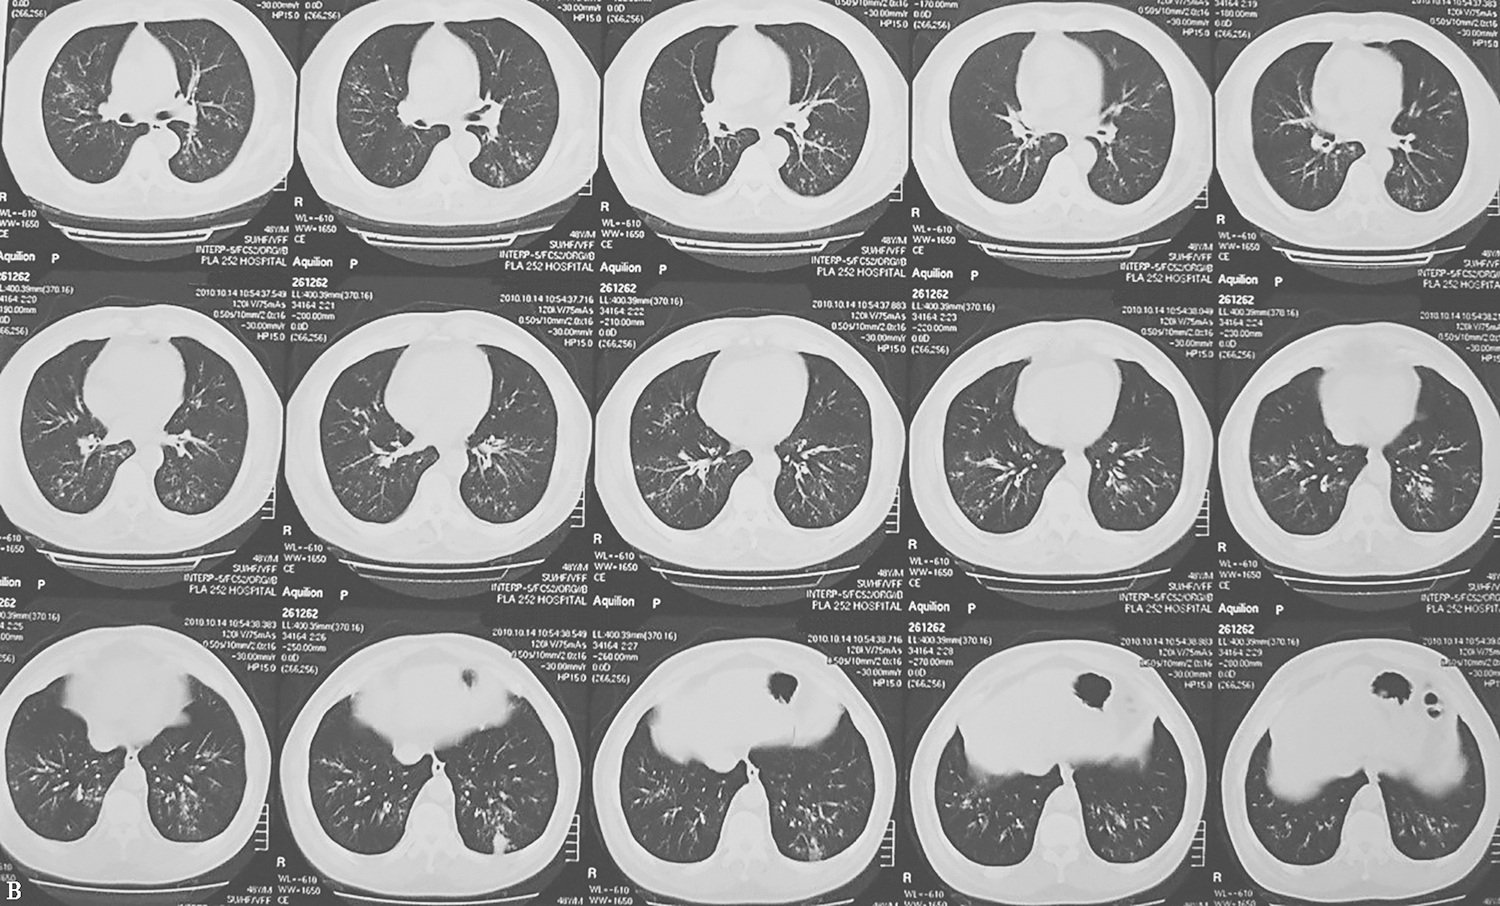

4.胸部CT表现为弥漫性细支气管炎、细支气管扩张(图1)。

图1 胸部CT表现(2011-12-28)

胸部CT显示双肺多发支气管壁增厚、管腔扩张,多发小叶中心性小结节影